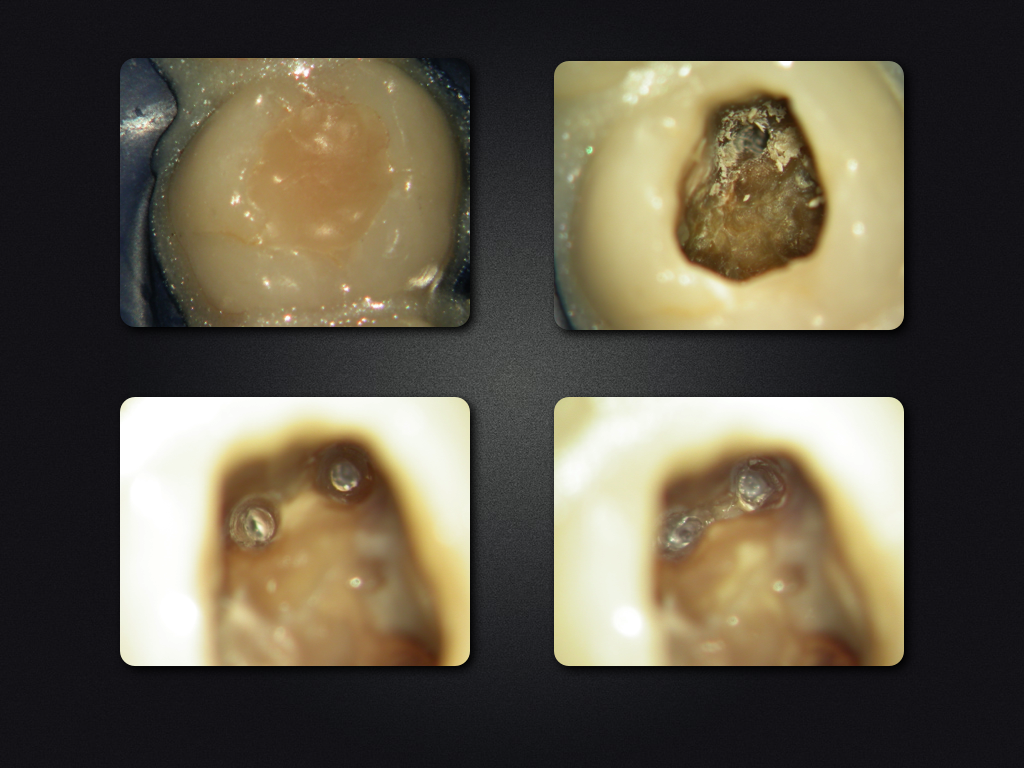

26D.006

Saving Hopeless Teeth (XXXII)